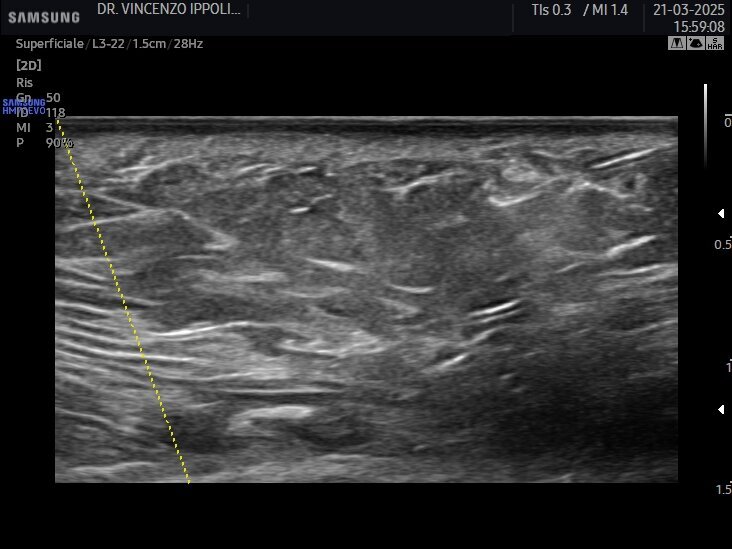

Gli ultrasuoni forniscono immagini in tempo reale con accuratezza variabile e dipendente dalle capacità dell’operatore e dalle potenzialità dell’apparecchiatura ecografica per uno studio accurato della cute e degli strati più superficiali del volto ma nascosti dall’epidermide (Fig. 1). Consentono una mappatura precisa delle strutture vascolari a prescindere dalle loro varianti anatomiche ed una valutazione della motilità dei piani muscolari. Ciò significa che con l’esame ecografico è possibile passare dall’osservazione anatomica statica a quella dinamica e valutare le straordinarie differenze ai fini diagnostici, esecutivi e post-operatori (Fig. 2) (clicca QUI e guarda il video). A causa della crescente popolarità delle procedure estetiche mininvasive al volto mediante tecniche iniettive/infiltrative/implantari, l’esame ecografico facciale è diventato fondamentale per tracciare i prodotti iniettabili, prevenire complicanze e, se necessario, riconoscerle per intervenire tempestivamente. Eventi avversi possono verificarsi al momento dell’iniezione, come le occlusioni o le compressioni vascolari, subito dopo il trattamento, come le infezioni, o diversi mesi dopo, come la comparsa di reazioni nodulari infiammatorie. Eseguire una metodica estetica al volto, sia essa infiltrazione di filler, iniezione intramuscolare di tossina botulinica o impianto di fili di trazione o di biostimolazione, sotto guida ecografica, fornisce un riscontro dinamico contestuale del posizionamento del riempitivo, consentendo al clinico di operare nell’area anatomica prescelta evitando sconfinamenti indesiderati (clicca QUI e guarda il video).

L’incidenza di complicanze vascolari dopo le iniezioni di filler pare essere 1/6600 (0,015%). Tuttavia, sebbene questo rischio non sembri molto elevato, anche un operatore esperto può incorrere in questo evento avverso. Se, da un lato, gli ultrasuoni possono aiutare nell’identificare e valutare il decorso dei vasi sanguigni a rischio di occlusione o compressione (Fig. 3), dall’altro, in caso di evento avverso correlato al filler a base di acido ialuronico, l’enzima ialuronidasi può essere iniettato con la guida degli ultrasuoni esattamente nel deposito del prodotto per una sua mirata dissoluzione (Fig. 4). Con l’avanzare dell’età, l’immagine della cute si modifica sia negli spessori sia nel numero degli annessi. L’esame ecografico contribuisce a visualizzare il progressivo deterioramento cutaneo: un assottigliamento del derma, la riduzione delle fibre collagene, la degenerazione delle fibre di elastina e la disidratazione influiscono sull’ecogenicità dei tessuti esaminati (Fig. 5).

Esame ecografico: quando Gli ultrasuoni – per mezzo dell’esame ecografico - sono usati in tutta le specialità della medicina come strumento diagnostico: non nocivo, indolore, affidabile e relativamente poco costoso, possono davvero agevolare l’Odontoiatra che intende esercitare la medicina estetica nel proprio studio professionale evidenziando inequivocabilmente l’anatomia degli spazi e delle strutture del volto, lo spessore dei tessuti molli, le immagini delle patologie che eventualmente si sovrappongono sul viso, la posizione dei vasi e l’andamento del flusso ematico nei vasi, la presenza di rami “importanti” del nervo faciale.

In più gli ultrasuoni possono valutare lo stato del filler – puro o prodotto in composti con altre sostanze – infiltrato al momento o in precedenza e guidare e seguire nel tempo procedure iniettive dell’anatossina botulinica, dei filler a base di acido ialuronico e l’impianto dei fili di trazione e di idratazione. Gli ultrasuoni sono davvero utili nel follow up dei pazienti, nella correzione dei casi clinici insoddisfacenti, nella gestione degli eventi avversi fra cui le complicanze (Fig. 6).

Accanto a immagini statiche di sicuro aiuto per i professionisti esperti della metodica, le immagini dinamiche rilevate nel corso delle procedure infiltrative per i filler, iniettive nel caso della tossina botulinica e implantari nel caso dell’impianto di fili di biostimolazione/idratazione e di fili di trazione/sospensione risultano assolutamente dirimenti sul giudizio di wellpractice o malpractice (clicca QUI e guarda il video). La differenza fra immagini statiche ed immagini dinamiche consiste proprio nella possibilità inopinabile di valutare nel corso della disamina dei filmati relativi all’esame ecografico rilevato simultaneamente all’iniezione, all’infiltrazione, all’impianto di tossina botulinica, di filler, di fili, se queste procedure sono state correttamente eseguite nelle varie fasi operative o viceversa.

Nel particolare l’esame ultrasonico registrato nei momenti in cui sono eseguite le procedure medicoestetiche – vero e proprio occhio di ciò che avviene al disotto della barriera cutanea – permette di rilevare senza dubbio alcuno:

l’adeguato spessore dei tessuti oggetto di trattamento e pertanto la giustificazione anatomica della proposta terapeutica dell’operatore (Fig. 1);

la struttura anatomica che accoglie il farmaco o il dispositivo medico;

la mappatura dei vasi della zona oggetto di intervento (Fig. 7 - clicca QUI e guarda il video; Fig. 8 - clicca QUI e guarda il video; Fig. 9 - clicca QUI e guarda il video);

la posizione della sonda che ha rilevato l’esame (body marker) (Fig. 10);

il risultato finale (Fig. 11).

L’esame ultrasonico nelle fasi successive all’intervento terapeutico – per mezzo di indagini statiche e specie con immagini dinamiche, permette di:

valutare l’andamento post-operatorio e la reazione visiva dei tessuti all’iniezione, all’infiltrazione e all’impianto;

valutare lo stato dell’azione del farmaco o del dispositivo medico nel tempo successivo alle procedure medicoestetiche;

valutare e gestire eventuali eventi avversi di tipo ischemico e di tipo non ischemico sempre possibili nei primi momenti post-operatori.